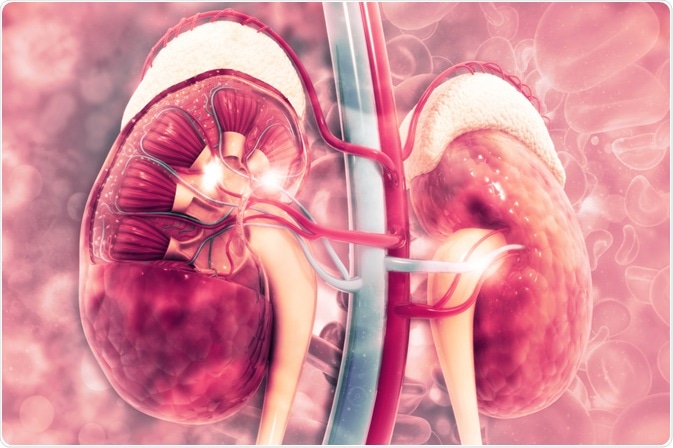

Chronic Kidney Disease (CKD): Primary And Secondary Prevention

Longstanding disease of the kidneys leading to renal failure.

The kidneys filter waste and excess fluid from the blood. As kidneys fail, waste builds up.

Treatment can help, but this condition can’t be cured

Requires a medical diagnosis

Lab tests or imaging always required

Chronic: can last for years or be lifelong